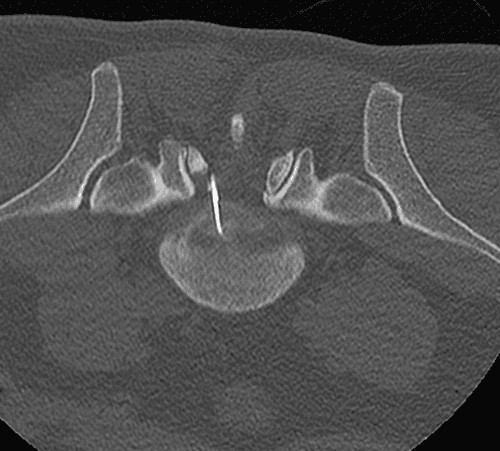

Technique de vissage percutané des fractures du toit du cotyle